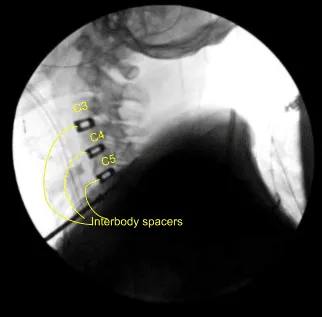

Bilateral foraminotomies were done using Kerrison punch 3.0. All the discs were thoroughly decorticated to achieve fusion. Once adequate foraminotomy and discectomy was done, a spacer was inserted to size the disc. After sizing, 8-mm Globus titanium cage filled with titanium interbody spacer, filled with autologous bone graft, mixed with Trinity and DBX was inserted finding it in adequate position.

Attention was moved to the C4-5 disc space. Caspar pin was inserted into the C5 body and expansion of C4-5 done with a self-retaining retractor. Skyline was moved inferiorly to retract medially and laterally. Discectomy was done in a similar fashion followed by excision of the posterior longitudinal ligament and bilateral foraminotomies. After adequate excision the sizing was done, Globus titanium spacer filled with Trinity and autologous bone graft and DBX was inserted again.

Again, a new pin was inserted into the C6 body and similar discectomy was done using curettes,matchstick bur and Kerrison punches. PLL was also excised. Bilateral foraminotomies of C5-6 was performed. A matchstick bur was used each time to make holes into the end plates for better fusion.

The cage was inserted, again packed with autologous bone graft, Trinity and DBX. After inserting all the three cages, the bony contouring was done using matchstick bur and plate was put of an adequate size. The plate was found to be adequate in AP and lateral views in a satisfactory position.